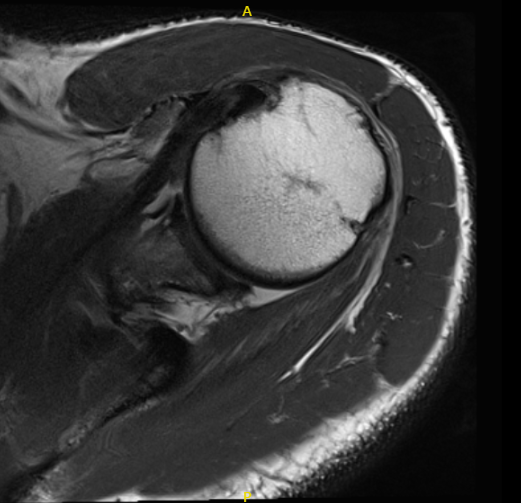

MRI of left shoulder

His MRI showed a complete tear of the supraspinatus tendon with 8 mm of medial retraction. Mild infraspinatus and long head biceps tendinosis and mild subacromial/subdeltoid and sub coracoid bursitis.

Mild AC arthrosis and degeneration of the superior posterior superior labrum. We discussed surgical and non-surgical treatment and the patient refused the surgery and wanted to give the conservative medication. Tramadol was prescribed for pain management.

MRI of left shoulder